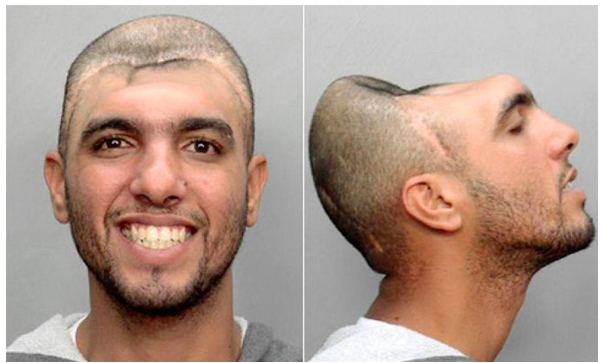

Еще один случай, американец по имени Карлос Родригес после несчастного случая живет практически без мозга. У него удалено больше 60% головного мозга, однако это не отразилось на его памяти и когнитивных способностях. Ему уже больше 35 лет

Уже к 14 годам на счету Карлоса Родригерса было несколько мелких или не очень нарушений закона. Угон автомобиля для него завершился аварией, которая сделала его человеком без мозга. Хирурги пытались спасти Родригеса 16 часов.

В итоге лобные доли мозга и часть черепной коробки пациента все-таки пришлось удалить, однако его сердце продолжало биться. Авария не стала уроком для Карлоса, который продолжил вести преступный образ жизни, употреблять наркотики и заводить бесчисленные половые связи. Удивительно, но у парня с весьма необычным внешним видом без мозга были целые толпы поклонниц.